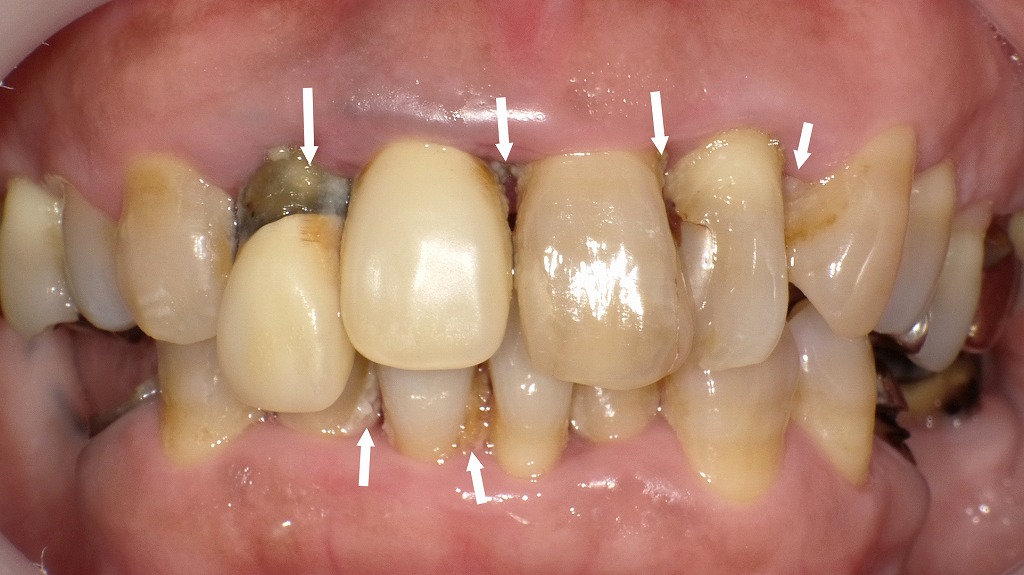

◆ 術前:歯石と古い差し歯で前歯が崩れた状態

この写真では、前歯に大量の歯石が付着し、歯の表面が黒く変色している部分が複数見られます。古い差し歯の境目には隙間ができ、そこから細菌が侵入して二次カリエス(虫歯の再発)が進行している状態です。また、歯ぐきは赤く腫れ、歯周病が進んでいるため、前歯が前方に押し出されるように傾いています。

歯石と歯周病によるダメージが重なり、見た目・噛み合わせ・清掃性のすべてが悪化していることがわかります。